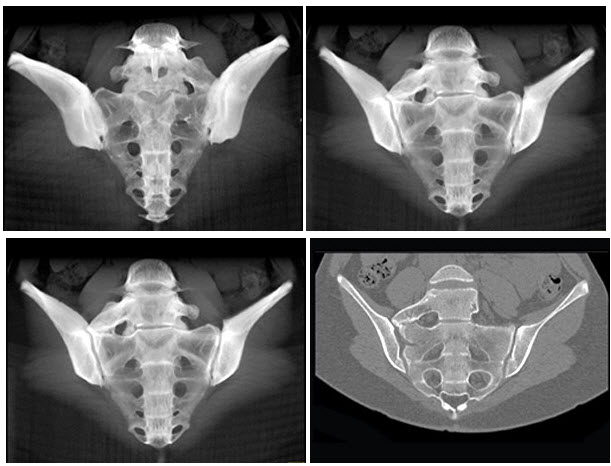

男,35岁,下腰部痛,L4-5棘突旁有明显压痛,结合图像,最可能的诊断是()

A . 压缩性骨折

B . 椎体融合

C . 腰椎骶化

D . 骶椎腰化

E . 退行性骨关节病

[单选题]男,35岁,下腰部痛,L棘突旁有明显压痛,结合图像,最可能的诊断是()A .压缩性骨折B .椎体融合C .腰椎骶化D .骶椎腰化E .退行性骨关节病